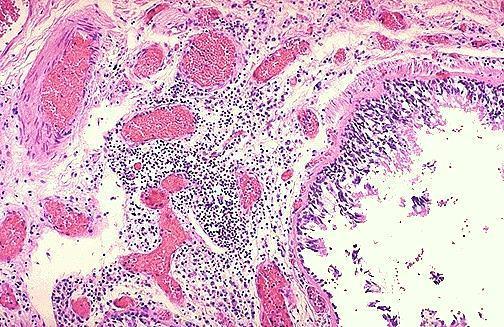

Aspecto macro e microscópico da pneumonia bacteriana.

- a colonização das superfícies bronquíolo-alveolares (normalmente estéreis) deflagra resposta inflamatória tipicamente supurativa;

- a exsudação resulta em edema pulmonar de extensão variável, com preenchimento alveolar-bronquiolar ("consolidação pulmonar") e prejuízos à ventilação e trocas gasosas;

- pode comprometer um ou múltiplos lobos, uni ou bilateralmente.